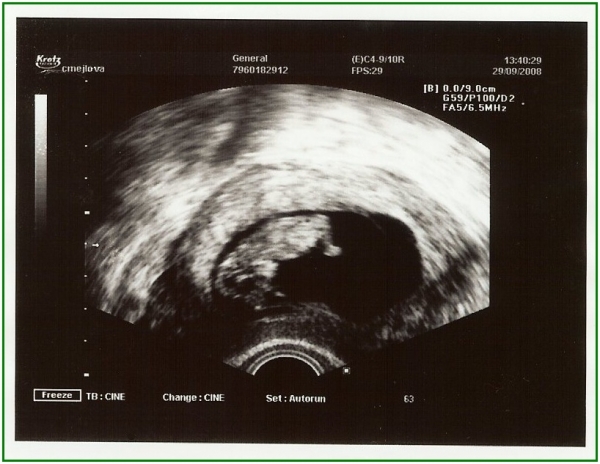

Pod pokličkou poprvé